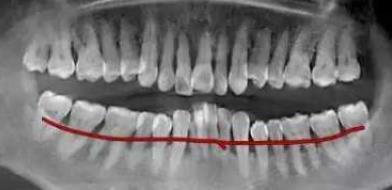

牙槽骨吸收嚴(yan) 重的牙片

全景片,和小牙片不同,是包含了全口牙齒影像的大片子,通常用於(yu) 需要評估全口牙齒和周圍頜骨情況時使用。